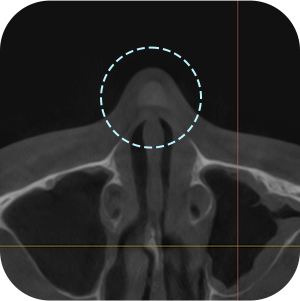

Memeriksa informasi implan dari operasi sebelumnya

Memeriksan masalah fungsional seperti deviasi septum

Memeriksa lokasi implan saat ini

Apakah perlu dilakukan CT scan hidung?

AKarena ini adalah operasi revisi, kita perlu mendiagnosis dengan lebih tepat!

Analisis menyeluruh penting untuk operasi revisi hidung .